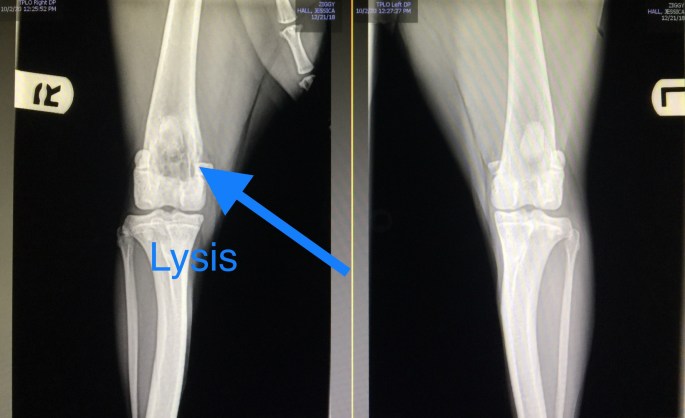

October 2, 2020 was the day we heard it was cancer. The bone in his hind leg was severely wasted away. Looking at the image, it doesn’t take a professional to see something wrong.

As the vet explained, lysis meant the bone was eaten away.

We were devastated. Ziggy wasn’t quite two years old. We were also in denial. While waiting for the oncologist’s consult, we again got a second opinion. We hoped that we’d find that it was a fungal infection, but that was an incredibly uncommon diagnosis given where we live.